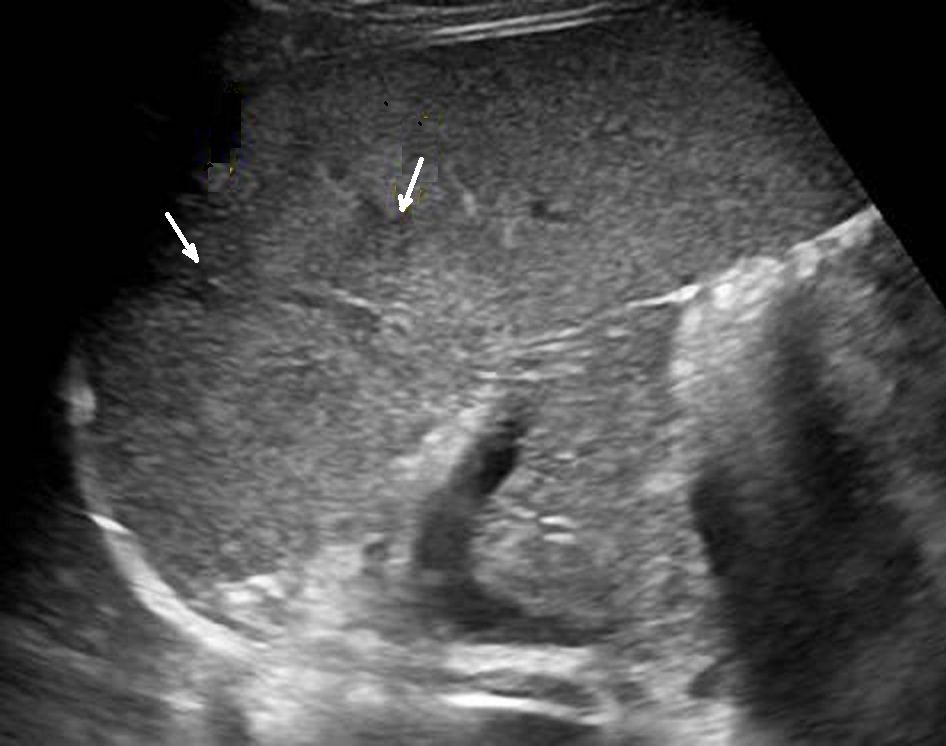

Image

echographique d'une traumatisme de la rate agrave a

grade II avec hematome sous capsulaire ( fleche

blanche ) et quelque zone de hypoechogene mal limite

intra parenchymateuse de la rate . |

Traumatisme de la rate grave ( grade IV ) avec

hematome intra parenchymateux marque ( fleche

blanche ) et dechirure capsulaire avec saignement

hilaire . Image de hemoperitoine localise a

inferieure de la rate peut en s'observer . Image

echographique en coupe longitudinale |